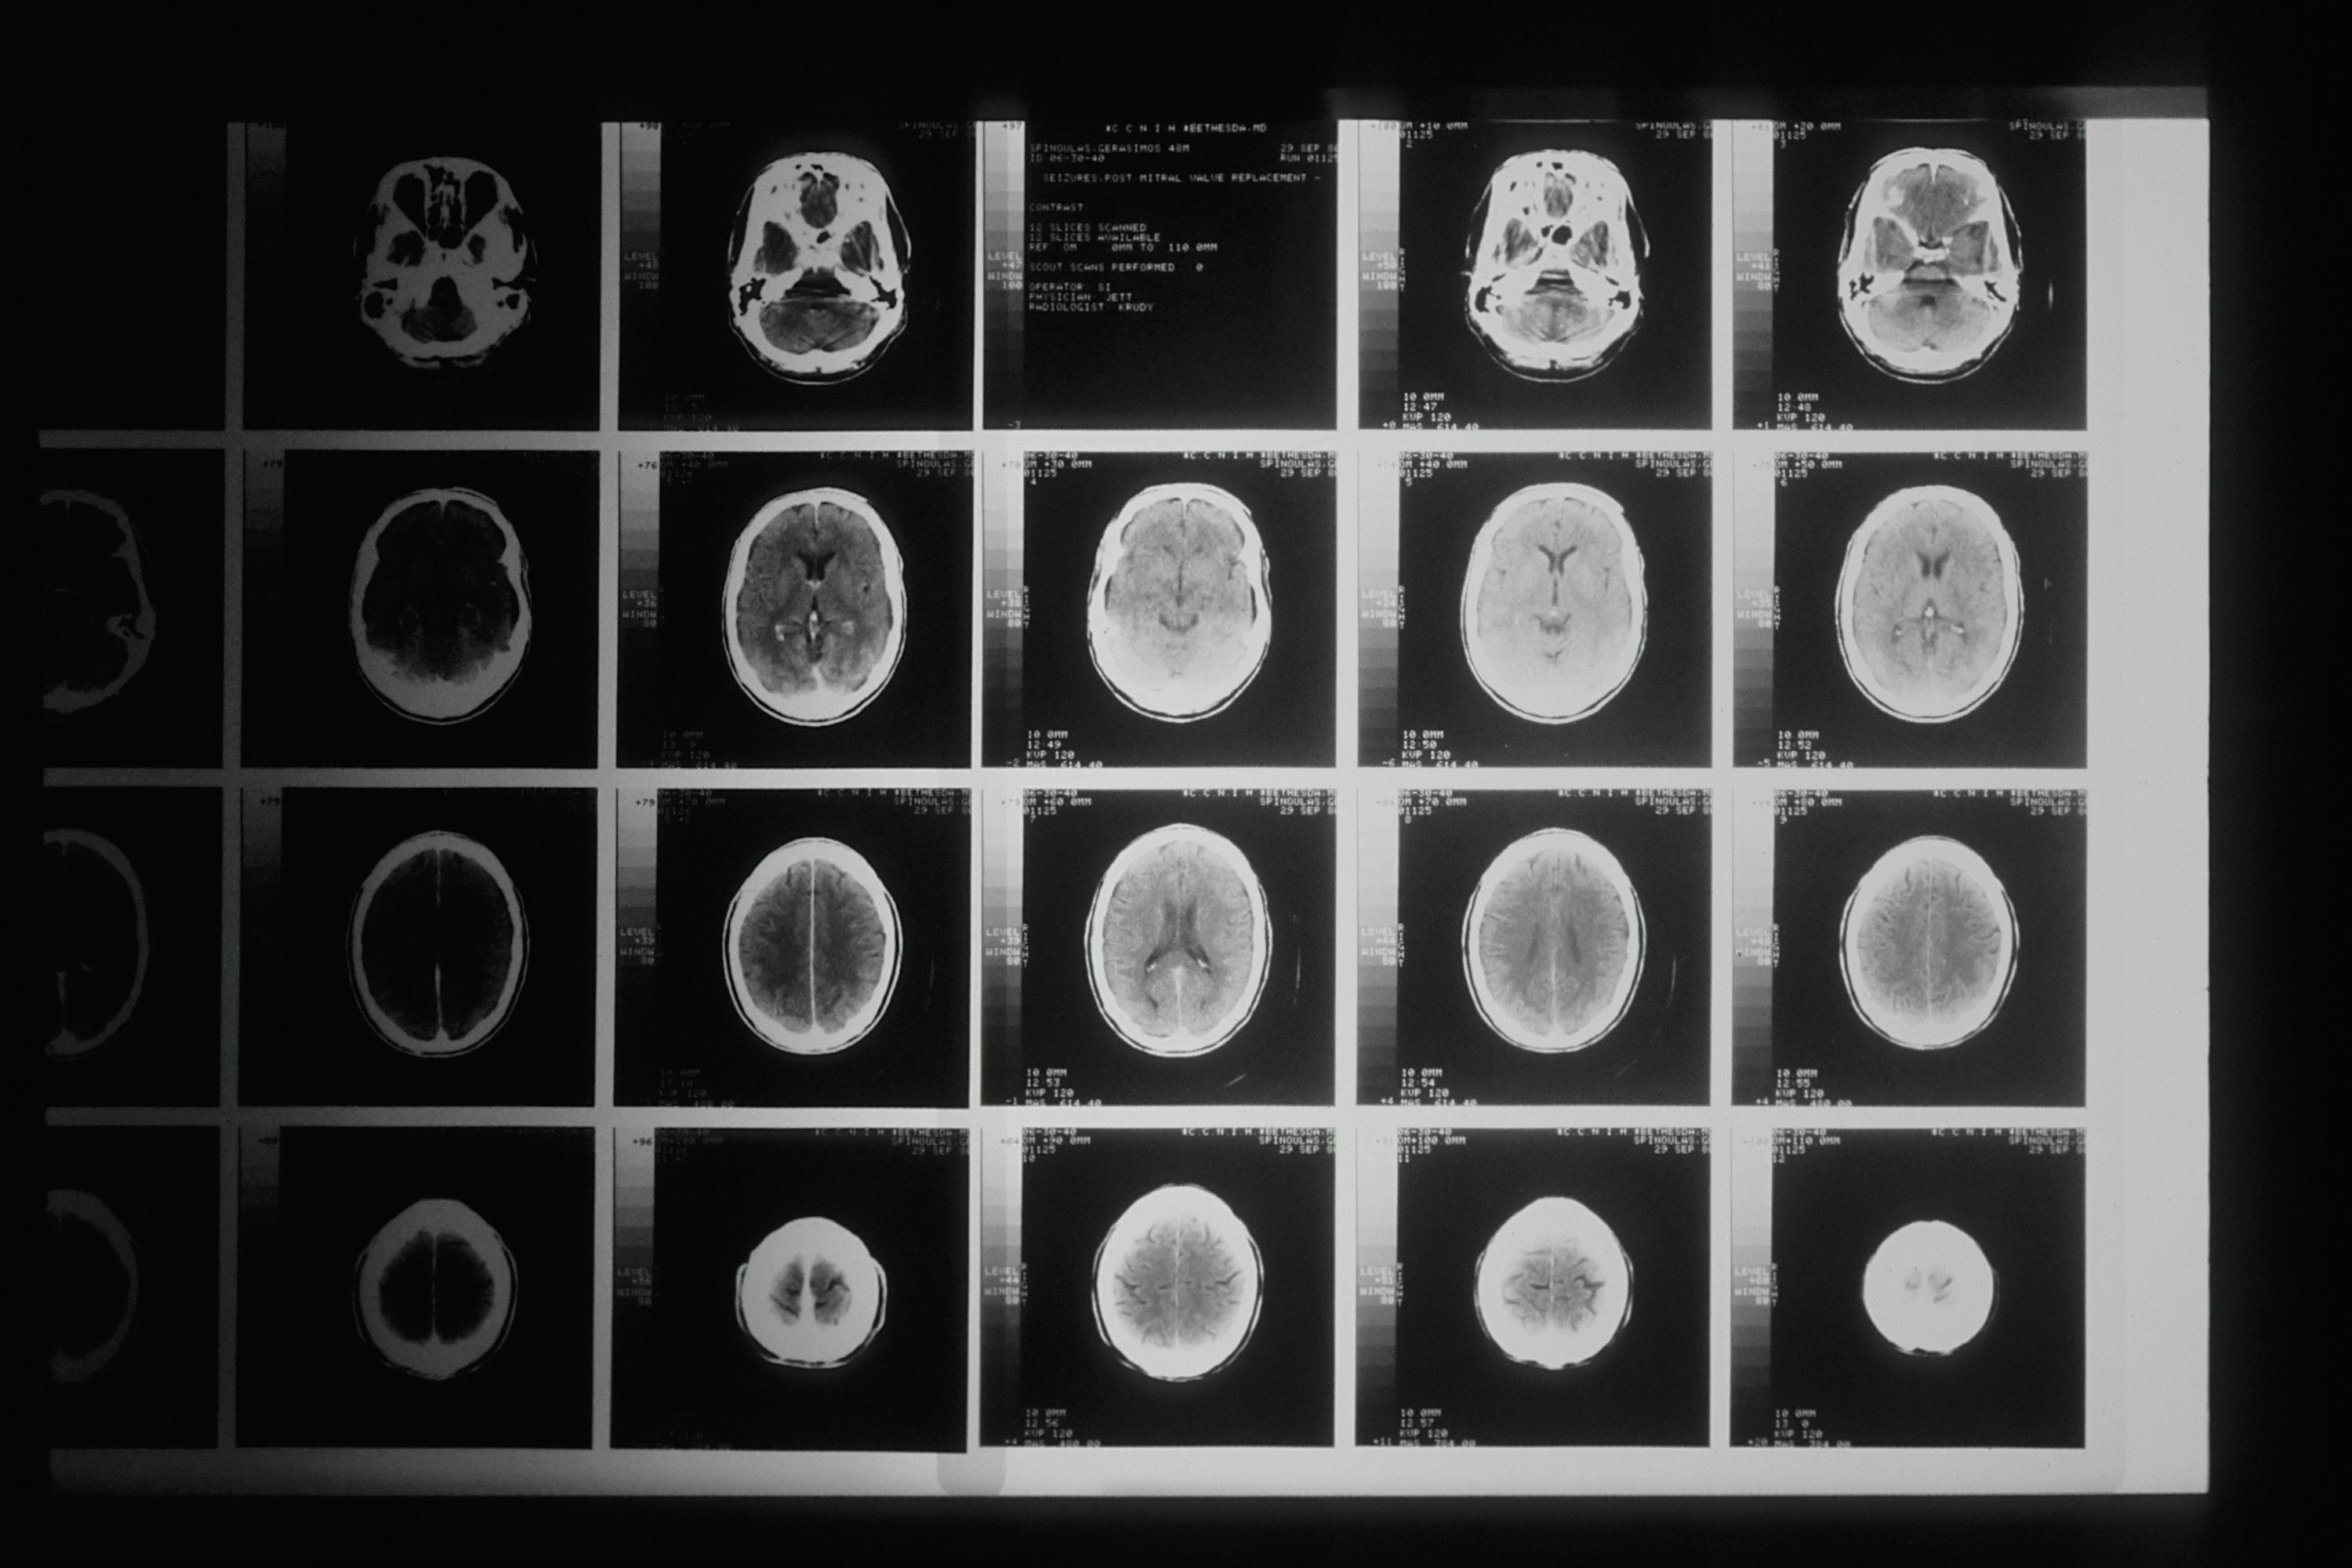

A. 두 질환의 초기증상은 매우 유사하여 증상만으로는 구별이 거의 불가능합니다. 다만 뇌출혈은 갑작스러운 극심한 두통, 구토, 의식 저하가 더 흔하고, 증상이 더 급격하게 악화되는 경향이 있습니다. 하지만 정확한 진단은 병원에서 CT나 MRI 검사를 통해서만 가능하므로, 증상이 나타나면 즉시 응급실로 가야 합니다.